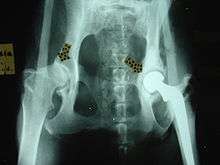

- For hip dysplasia:

- Femoral head ostectomy

- Triple pelvic osteotomy

- Hip replacement